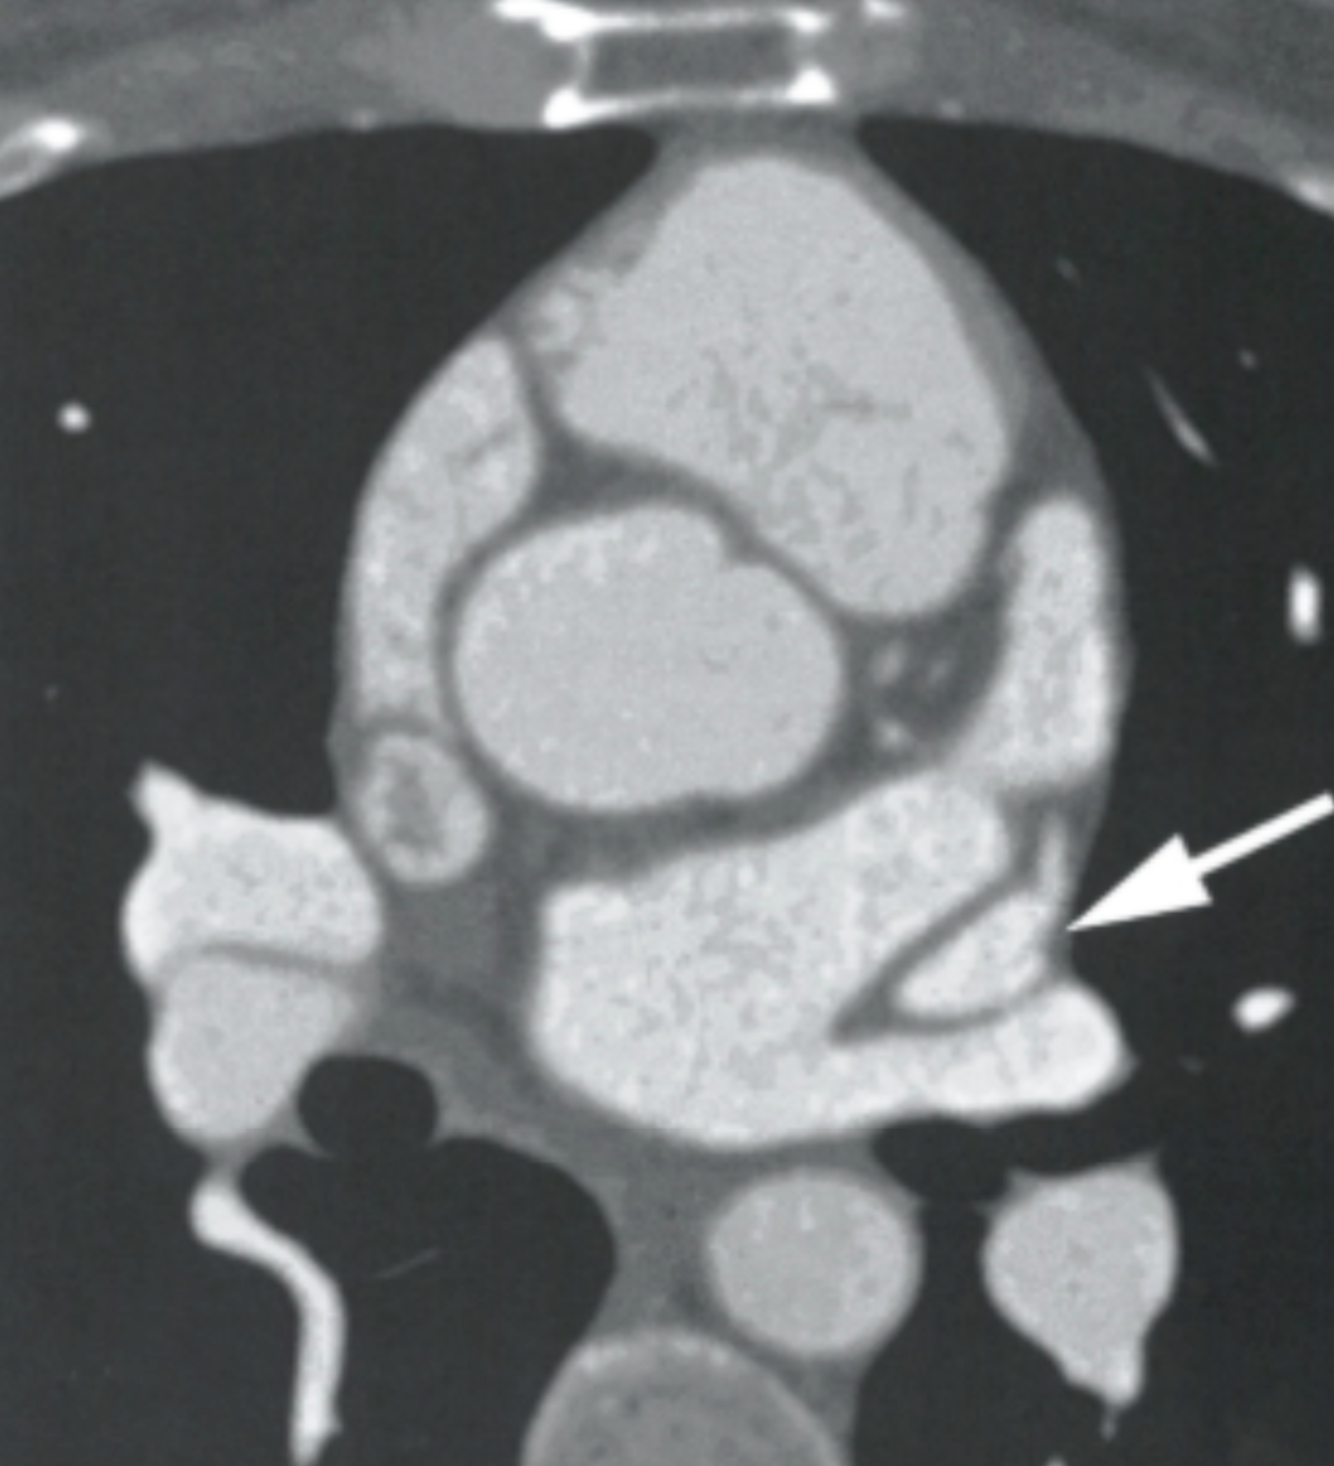

Describe the findings

Myxomatous disease of the mitral valve

What are the best views to confirm mitral valve prolapse on cardiac CT?

3-chamber view or PLAX view